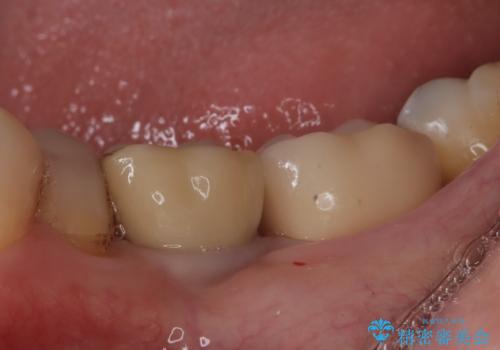

メタルインレーの下は。クラックラインを認めた歯。

- 定期検診にて、奥歯にクラックラインを認めました。

放置すると、抜歯になる可能性も高いため早めの治療を提案し、クラウンにて修復治療を行なっております。

術前説明にてクラックラインを認めることや治療の選択肢及び予後について理解していただいた上で、保存を希望されております。歯髄症状が出なかったため抜髄はせずに治療を完了しております。